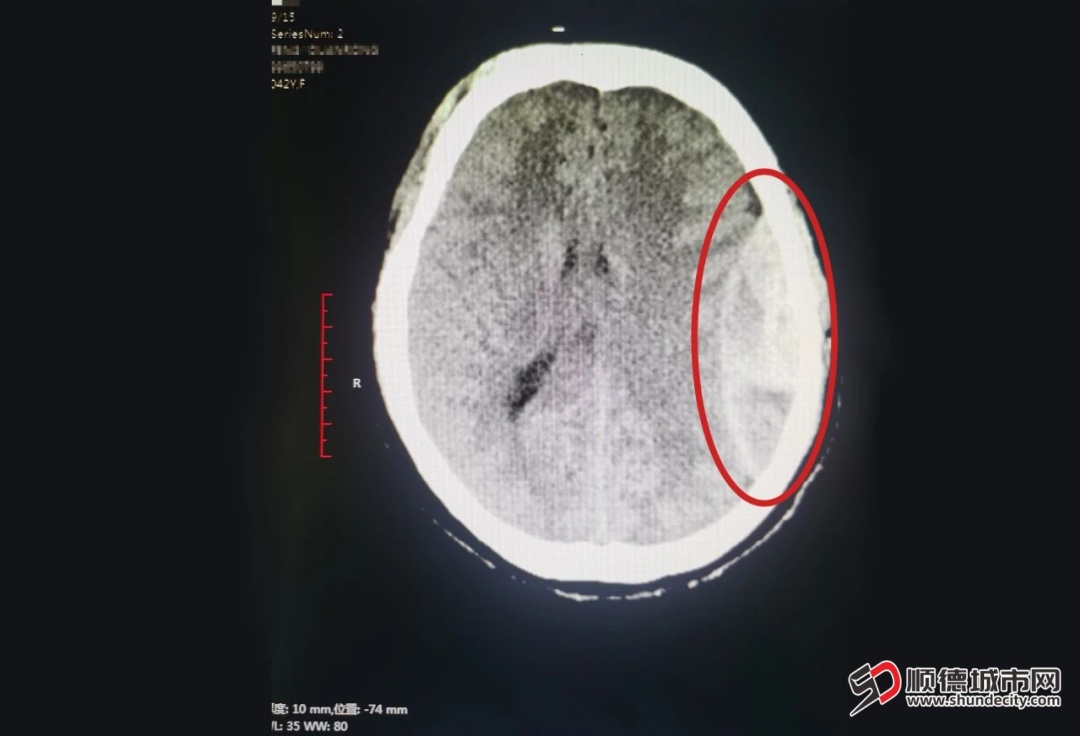

术前CT,严重颅内出血。

2025年5月22日17时30分,一名42岁女性从3米高处坠落,头面部大量出血,被紧急送往顺德和平外科医院。到院时患者已出现休克及昏迷,头颅CT显示严重颅内出血,病情危急。医院立即启动多学科救治预案,麻醉手术科、神经外科、检验科等团队迅速到位展开抢救。